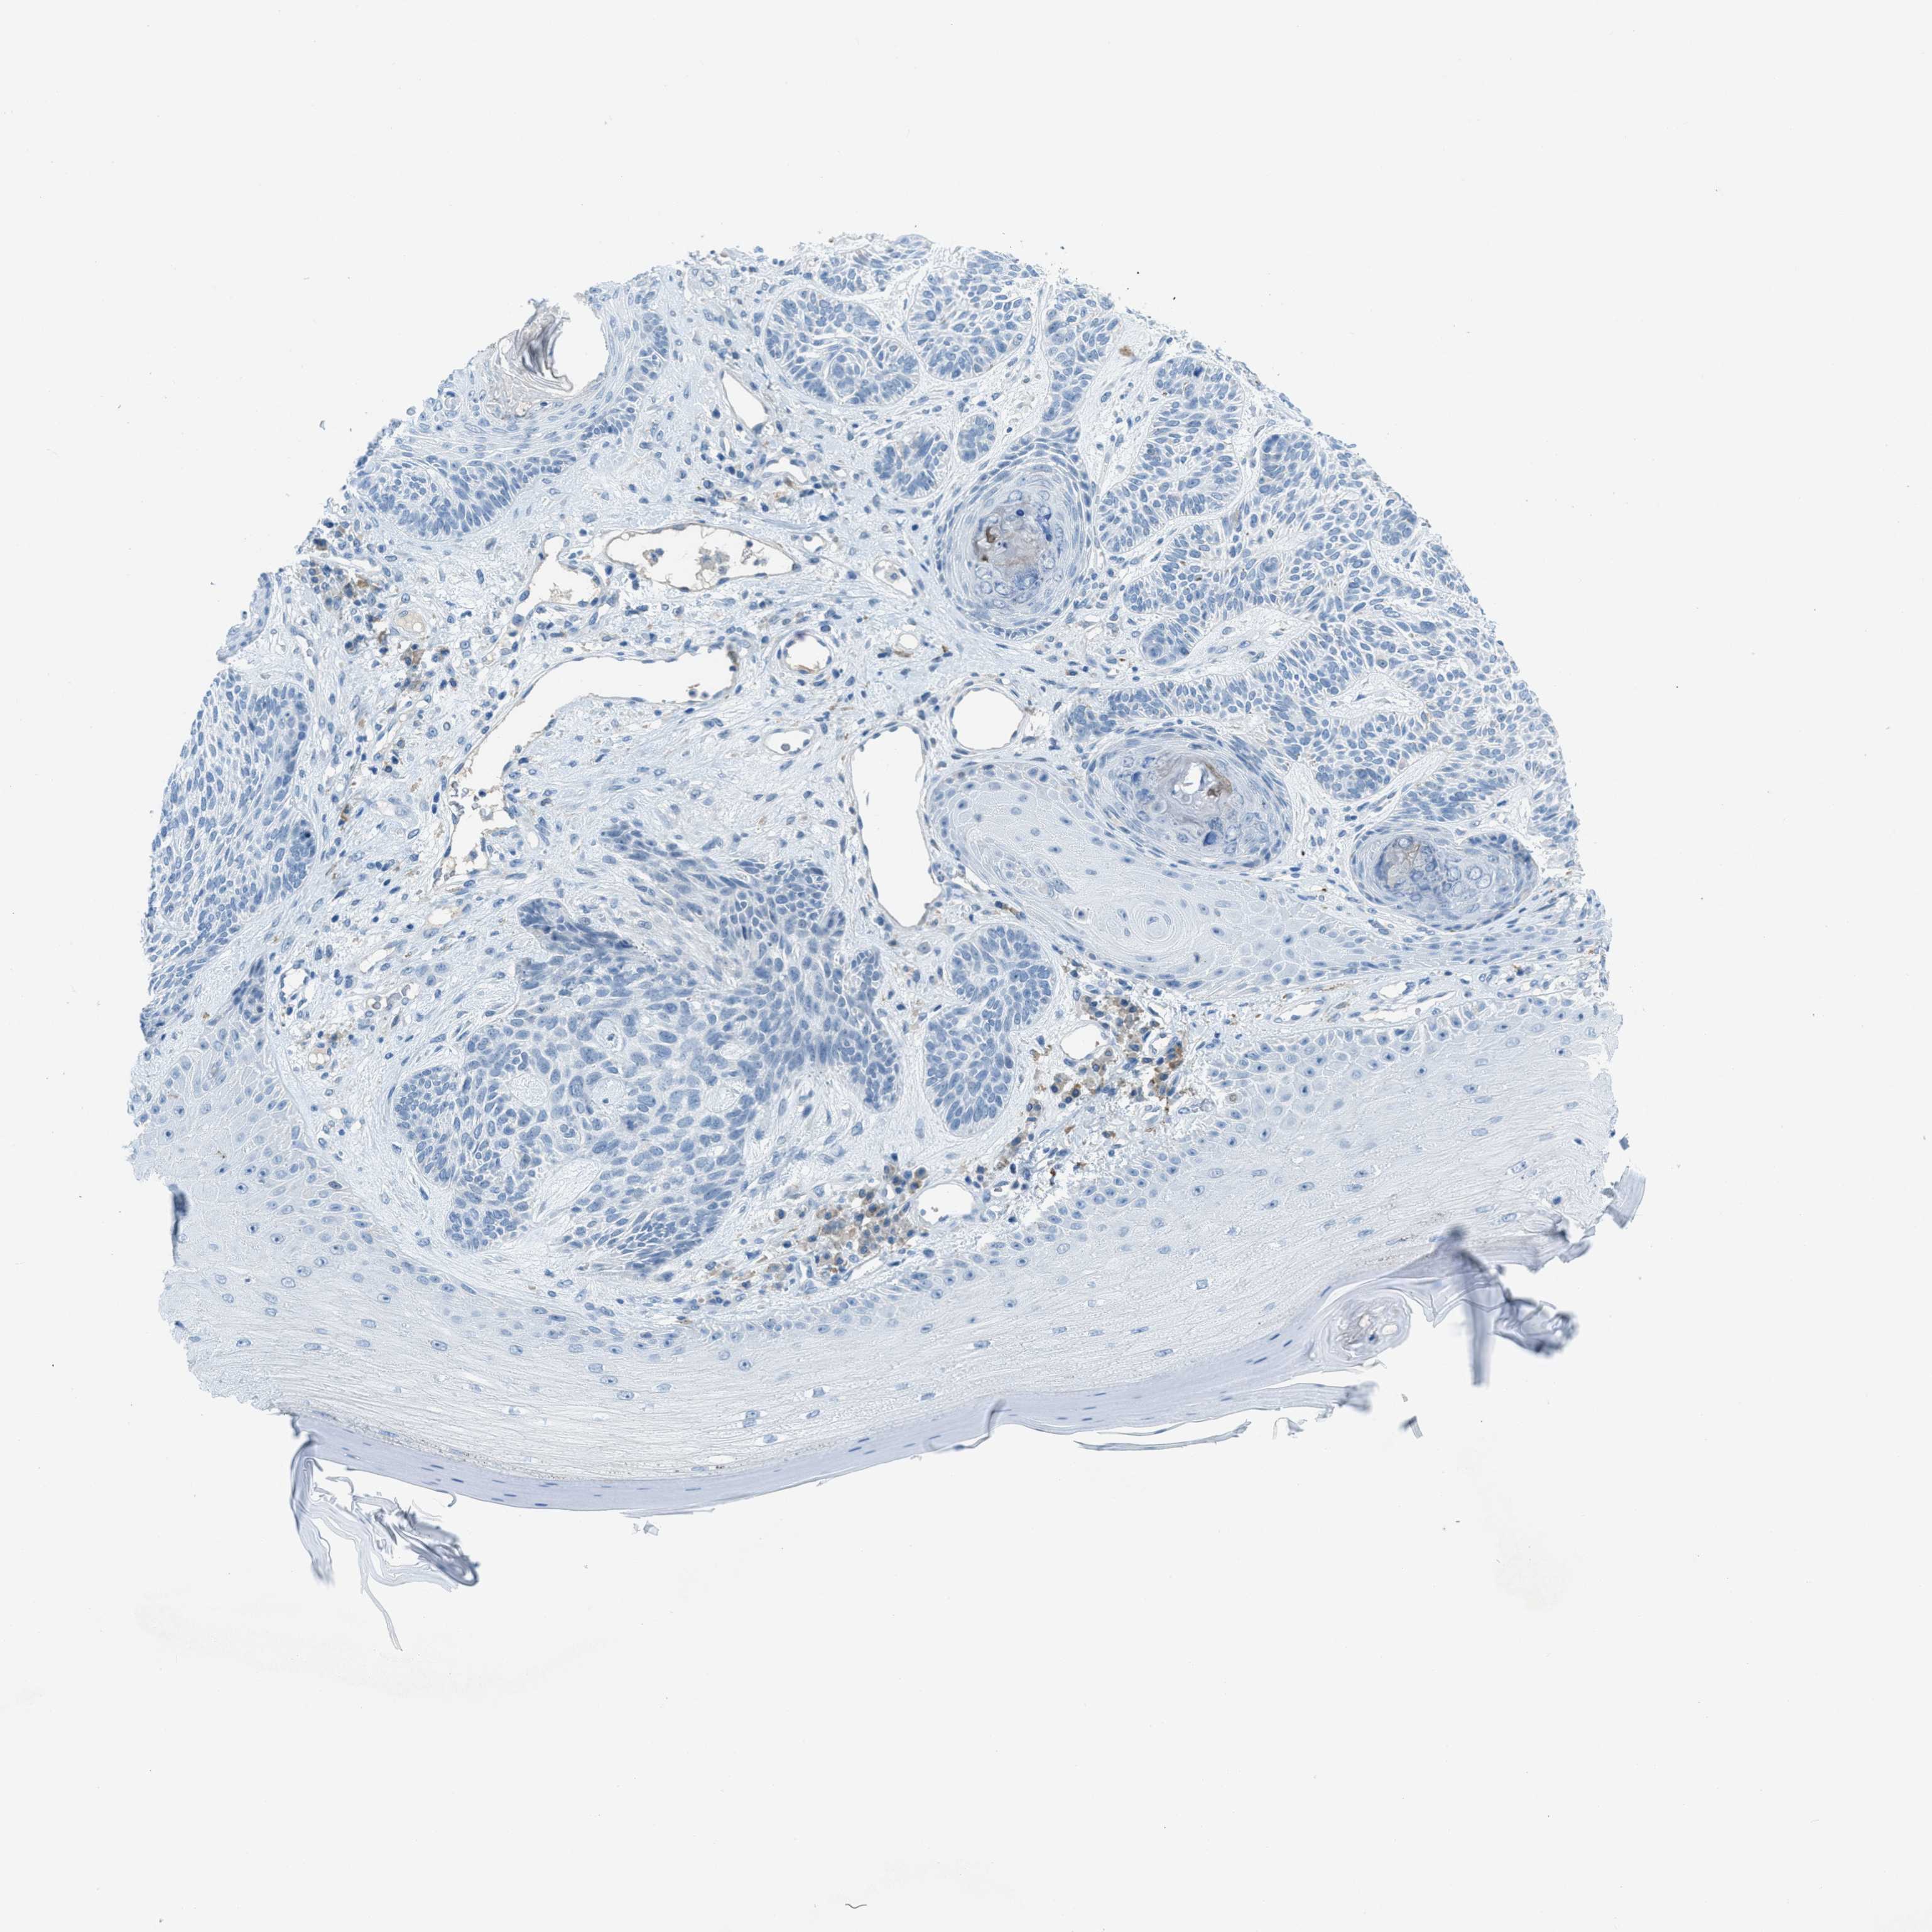

SKIN CANCER - Protein expressioni

A mouse-over function shows sample information and annotation data. Click on an image to view it in a full screen mode. Samples can be filtered based on level of antibody staining by selecting one or several of the following categories: high, medium, low and not detected. The assay and annotation is described here.

Each image is clickable and will lead to virtual microscopy that enables deeper exploration of all samples and also displays staining intensity scores, fraction scores and subcellular localization as well as patient and tissue information for each sample.

Antibody HPA013856

Squamous cell carcinoma, NOS